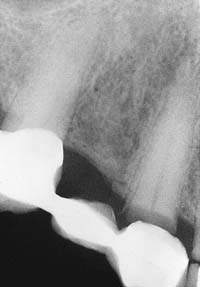

If the patient has several endodontically treated teeth that have been restored with posts and cores and with fixed prostheses, the possibility of root fracture should be considered, especially for teeth that were internally weakened as a result of endodontic treatment in conjunction with oversized posts of suboptimal length. If a fracture has occurred, the tooth is almost invariably lost, which can significantly complicate follow-up treatment, especially if it involves an abutment tooth for an FDP (Fig. 32-18).

An improperly fabricated connector may fracture under functional loading (Fig. 32-26). Depending on the design and location of the FDP, the patient may complain of varying degrees of pain. Extra force is typically transmitted to the abutment teeth, and discomfort from overloading the periodontal ligament may draw attention away from the location of the actual problem. If the abutment teeth have good bone support and minimal mobility, fractured connectors can be very difficult to detect clinically. Wedges can sometimes be positioned to separate the individual FDP components enough to confirm the correct diagnosis.

Detecting disease around an FDP can be extremely difficult at a stage when corrective treatment is still relatively simple. For instance, partial dissolution of the luting agent may be difficult to diagnose with a subgingival margin. Caries is often detected only after irreversible pulp involvement has resulted. Caries under a crown is more difficult to detect radiographically, although bitewing images provide some information interproximally. Follow-up studies on patients with FDPs reveal that identifying risk factors and predicting the development of caries in any particular patient are complicated. However, there is no indication that caries is more likely in association with prostheses than on unrestored teeth.3

If caries is overlooked, disease may rapidly progress to the point at which the fabrication of a new prosthesis becomes inevitable or, even worse, tooth loss results.